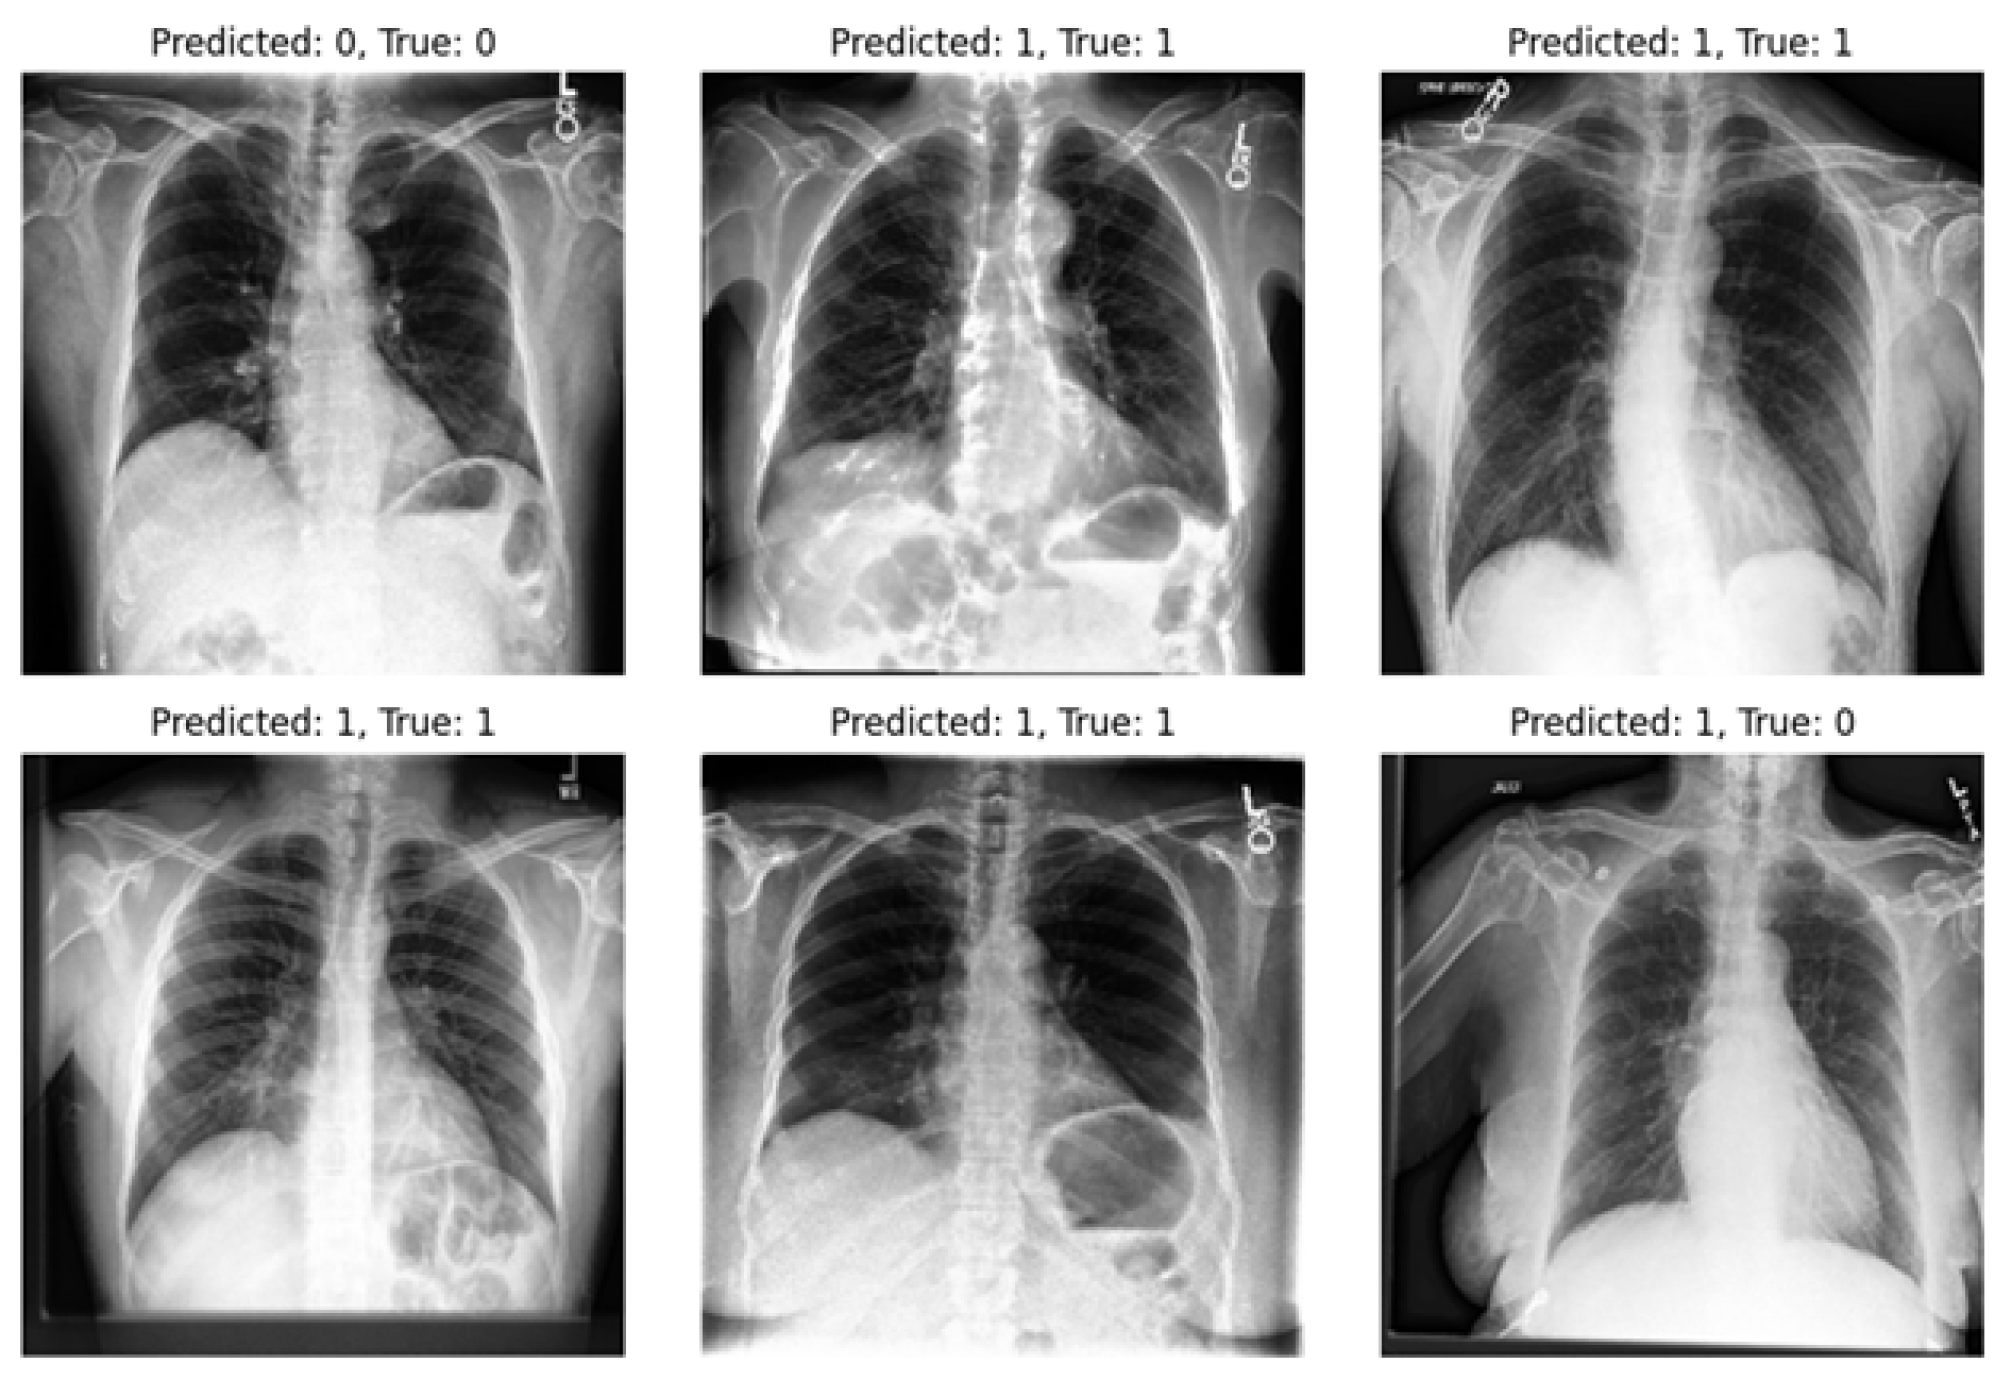

Our study underscores the pivotal role of multi-view X-rays in augmenting the reliability of disease diagnosis, particularly in the case of pneumonia. Our experiments validate the significance of incorporating lateral-view X-rays alongside frontal ones for more comprehensive assessments, thereby enhancing the overall reliability of the diagnostic process and facilitating more confident clinical decisions. By integrating latent representations derived from both the VAE and β -VAE models, our approach significantly enhances diagnostic outcomes in pneumonia classification tasks. On the other hand, we highlight one of the limitations of our experiments: the imbalance within our dataset. Notably, in the experiments, the number of positive samples was twice that of negative samples. This imbalance stemmed from the scarcity of images devoid of the disease and offering diverse viewpoints within the dataset. The classifier’s performance is illustrated in Figure 9 and Figure 10, revealing instances where the model erroneously classified negative images as positive when evaluating the test set. Despite these challenges, our methodology shows promising performance and yields satisfactory results compared to previous studies.

Figure 9. Utilizing a classifier to predict frontal images from the test set.

Diagnostics 14 01566 g009